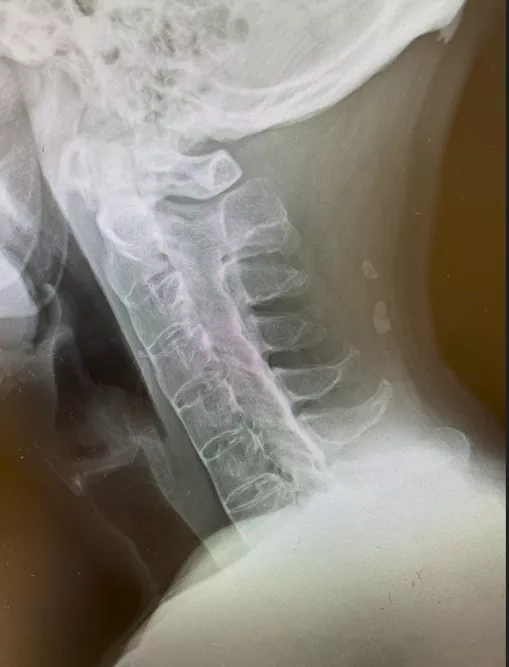

写真2 単純X線 頸椎側面像

椎体辺縁に沿った硬化像を認める

若年男性に発症した、運動により改善して安静により改善しない3か月以上持続する炎症性腰背部痛の所見と血清反応陰性、CRPの上昇より脊椎関節炎を疑った。単純X線では両側仙腸関節に関節裂隙全体の強直を認めgrade4の仙腸関節炎の所見であった(写真1)。また、同写真で腰椎の椎体辺縁に沿った硬化像も認めた(写真1)。追加で行った頸椎(写真2)、胸椎(写真3)、腰椎(写真4)単純X線の側面像では全脊椎の強直(竹様脊椎、bamboo spine)を認めた。以上より強直性脊椎炎と診断した。